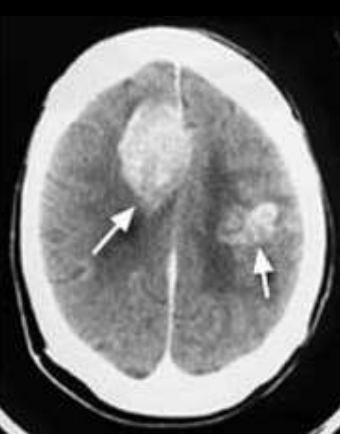

<p>Estudio y nomenclatura</p>

Estudio y nomenclatura

TC, Hiperdensos.